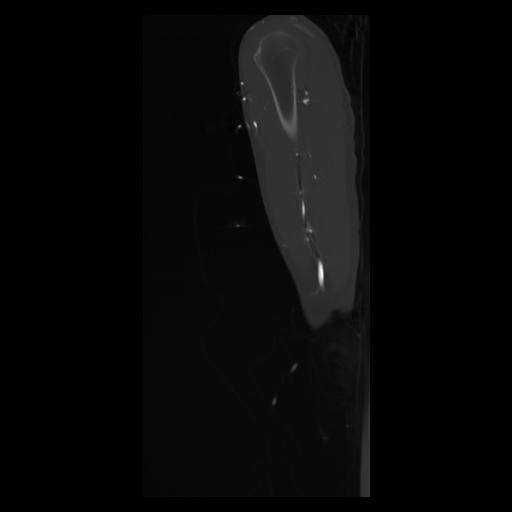

30 CUERPO,CE,Sagittal,3.000,CUERPO,Sagittal,